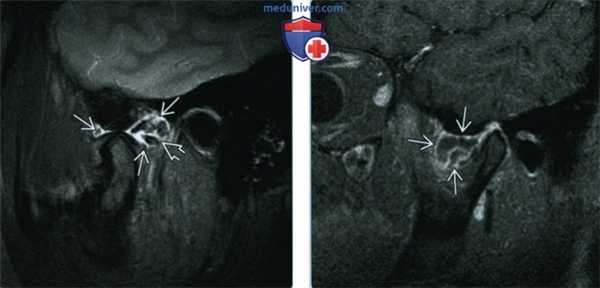

(Слева) При MPT T2FS в кососагиттальной проекции определяется растяжение капсулы правого височно-нижнечелюаного сустава с наличием обызвеавленных свободных тел с низкой интенсивностью сигнала, окруженных жидкостью с гиперинтенсивным сигналом.

(Справа) При МРТ Т1ВИ FS с КУ в сагиттальной проекции в передних отделах ВНЧС визуализируется кистозное образование, накапливающее контраст по периферии в виде «ободка». Верхнее суставное пространство расширено. Периферический «ободок» представляет собой синовиальную оболочку, накапливающую контраст.

4. МРТ при синовиальном хондроматозе височно-нижнечелюстного сустава:

• Т1ВИ:

о Множественные гипоинтенсивные узелки в верхнем суставном пространстве

о Отделение внутрисуставного диска

• Т2ВИ:

о Выпот в верхнем суставном пространстве выражен больше, чем в нижнем ± расширение

о Скопления узелков с гипоинтенсивным сигналом, окруженных жидкостью

• Т1ВИ с контрастным усилением:

о Накопление контраста в синовиальной оболочке